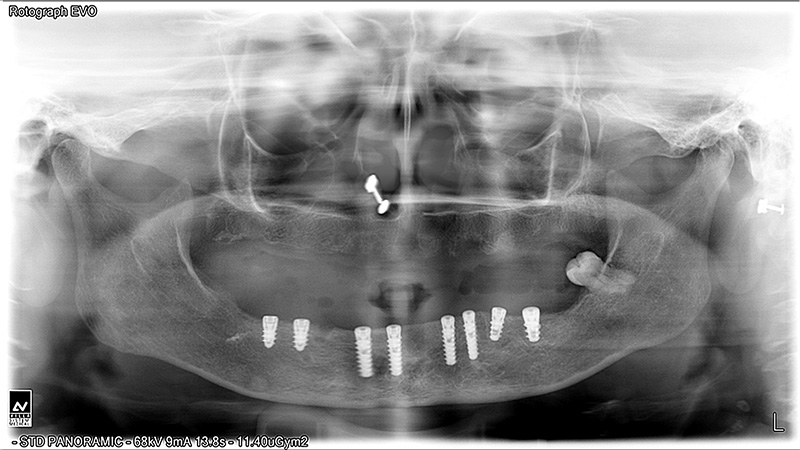

Implants

Implant Patients